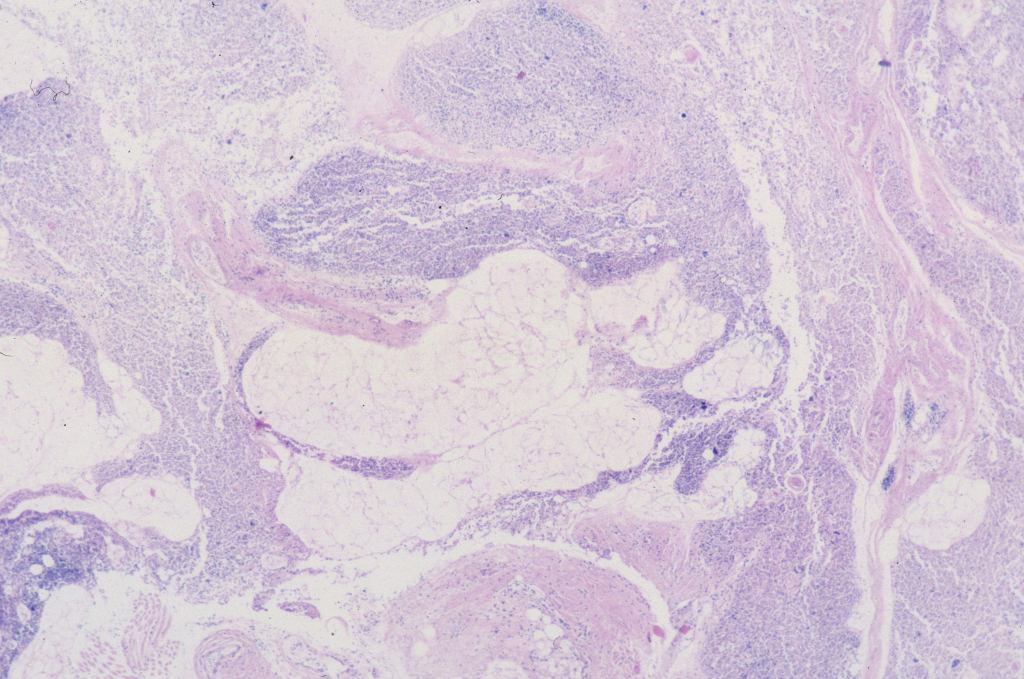

The complexity of thymic changes is demonstrated in a case of a 22 week gestation infant with a week of preterm premature rupture of membranes who was treated with betamethasone (a synthetic corticosteroid that can cross the placenta to the infant and used to promote lung maturation) and antibiotics. The infant survived for three quarters of an hour. The placenta demonstrated choroamnionitis with some fetal inflammation in the superficial chorionic vessels. The autopsy demonstrated complete involution of the thymus, follicular formation in the spleen, and extensive, intense acute pneumonitis with no growth of microorganisms on lung culture. The thymus demonstrated an inverted picture with no cortex and small lymphocytes in the medulla. The cortical rim demonstrated a compact epithelial layer. (Figs 16, 17) This infant had evidence of acute inflammation, and antibody stimulation, making it impossible to assess the changes due to the exogenous steroid.